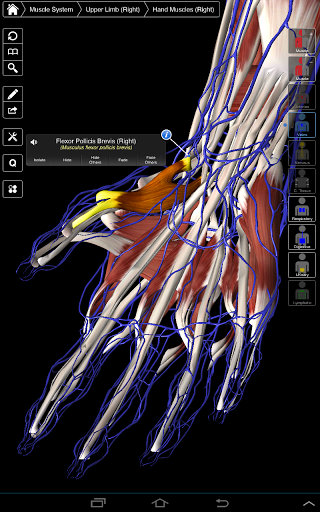

Essential Anatomy 3 representa lo último en tecnología 3D innovadora y diseño innovador. Un motor de gráficos 3D de vanguardia, creado a medida por 3D4Medical desde cero, alimenta un modelo anatómico altamente detallado y ofrece gráficos de calidad excepcional que ningún otro competidor puede lograr.

La aplicación representa un enfoque único para el aprendizaje de la anatomía general. Los gráficos no tienen paralelo y hacen que el aprendizaje, a través del uso de contenido informativo y características innovadoras, sea una experiencia rica e interesante.

⁃Músculos

NUEVA TECNOLOGÍA 3D

Essential Anatomy 3 es receptivo, visualmente impactante y sin esfuerzo. La aplicación es totalmente en 3D, lo que significa que puedes ver cualquier estructura anatómica de forma aislada y desde cualquier ángulo.

---- Más de 4,000 estructuras anatómicas altamente detalladas

---- Modo de selección múltiple - Ocultar / Fundir / Aislar estructuras individuales o múltiples